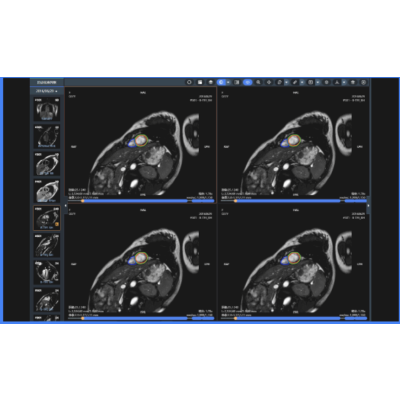

心肌病变辅助诊断

应用MR影像,针对心脏MR长轴2腔、3腔、4腔,短轴电影序列等多模态影像数据,快速完成心脏MR影像定量分析,输出射血分数、容积、排空率、充盈率等多项心功能指标,智能评估左心室各段心肌运动功能;同步实现心肌梗死、扩张性心肌病、肥厚型心肌病等心肌病变辅助诊断。